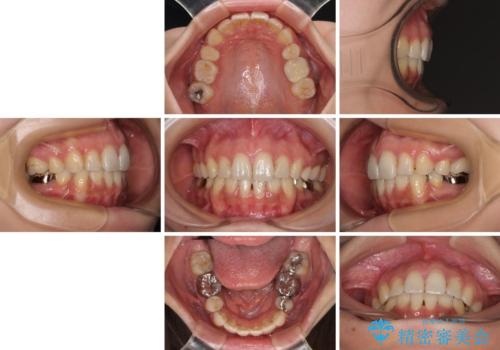

デコボコと口元の突出感 ハーフリンガルでの抜歯矯正

- 前歯のデコボコと上顎の前突感による口の閉じにくさを気にして来院された患者様です。

目立たない装置を希望されたので、上顎が裏側装置のハーフリンガルを選択し、上下左右の小臼歯(計4歯)を抜歯して矯正治療を行うこととしました。

表側のワイヤー矯正に比べると治療期間は長く、費用も高額となりますが、どうしても目立たせたくないという方にはお勧めの抜歯矯正です。